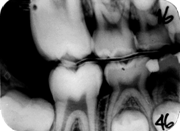

-46, suprafata meziala - radiotransparenta limitata in smalt - scor radiologic 1

- 45, suprafata distala - radiotransparenta in smalt pana la jonctiunea smalt-dentina, scor radiologic 2